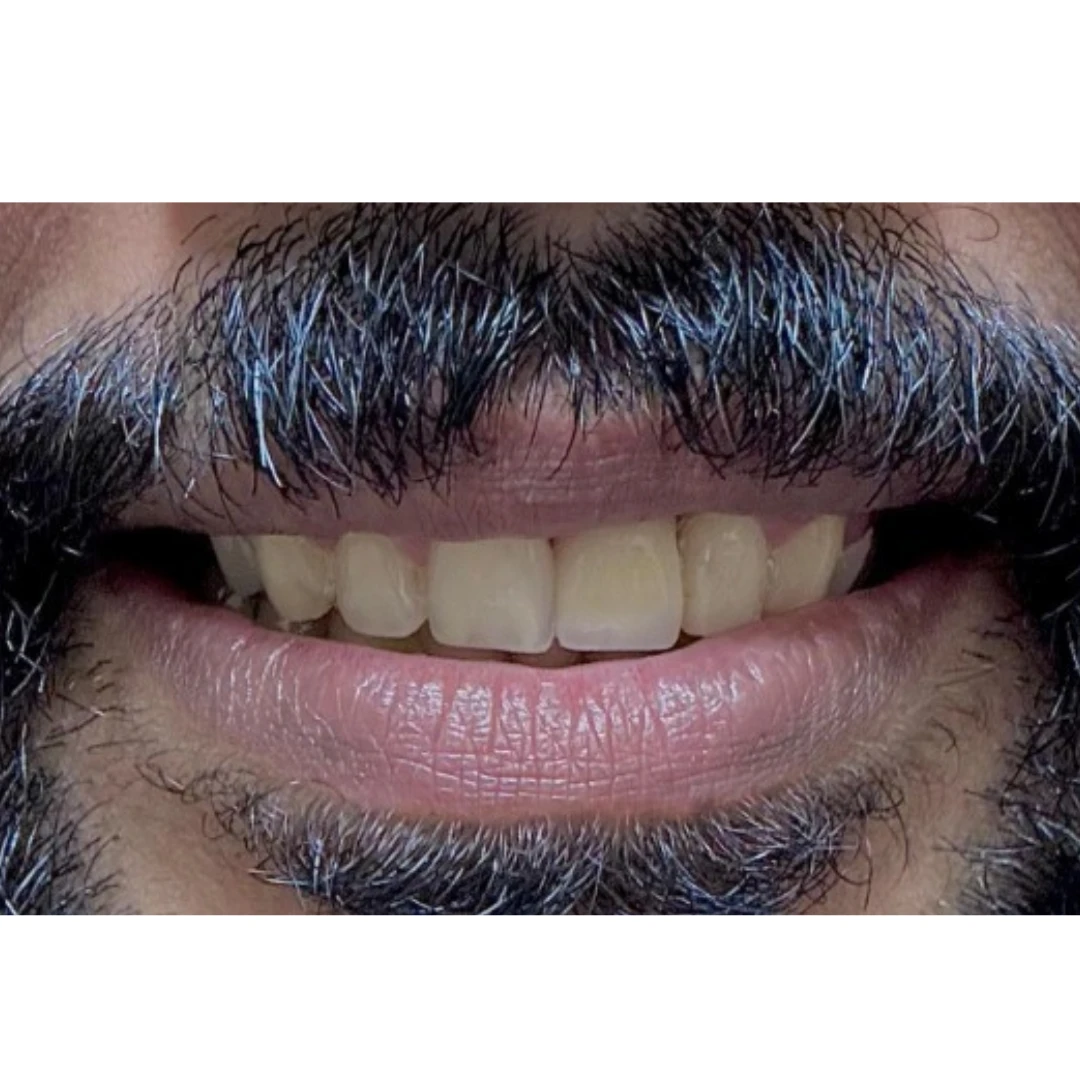

After

Before